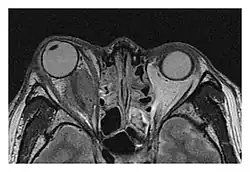

Right optic disc lesion in IgG4-ROD

Mass lesion around the right optic disc in a 44-year-old man with IgG4-related ophthalmic disease and a serum IgG4 of 599 mg/dL.[1] (T2-weighted MRI)

The extent of inflammation that can occur in IgG4-ROD is well demonstrated on magnetic resonance imaging (MRI).